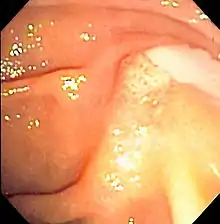

Duodenoscopy image of pus extruding from the ampulla of Vater, indicative of cholangitis

The gold standard test for biliary obstruction is still endoscopic retrograde cholangiopancreatography (ERCP). This involves the use of endoscopy (passing a tube through the mouth into the esophagus, stomach and thence to the duodenum) to pass a small cannula into the bile duct. At that point, radiocontrast is injected to opacify the duct, and X-rays are taken to get a visual impression of the biliary system. On the endoscopic image of the ampulla, one can sometimes see a protuberant ampulla from an impacted gallstone in the common bile duct or the frank extrusion of pus from the common bile duct orifice. On the X-ray images (known as cholangiograms), gallstones are visible as non-opacified areas in the contour of the duct. For diagnostic purposes, ERCP has now generally been replaced by MRCP. ERCP is only used first-line in critically ill patients in whom delay for diagnostic tests is not acceptable; however, if the index of suspicion for cholangitis is high, an ERCP is typically done to achieve drainage of the obstructed common bile duct.[1]